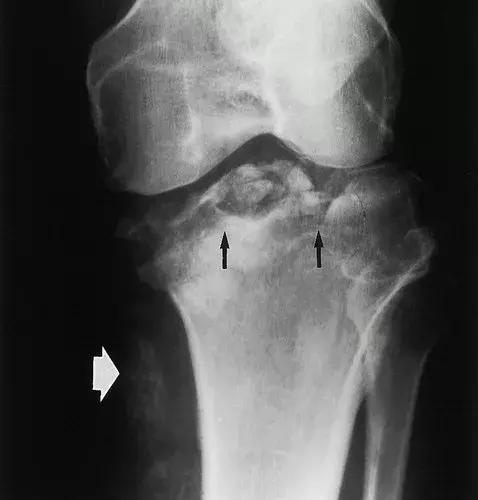

图8:50岁男性,三期梅毒,膝关节的神经性骨关节病。X线片显示胫骨平台受到冲击和破碎(黑色箭头)。在小腿内侧(白色箭头)软组织内可见骨碎片,远离关节。 (来自ACR学习档案,MSK案例234.)